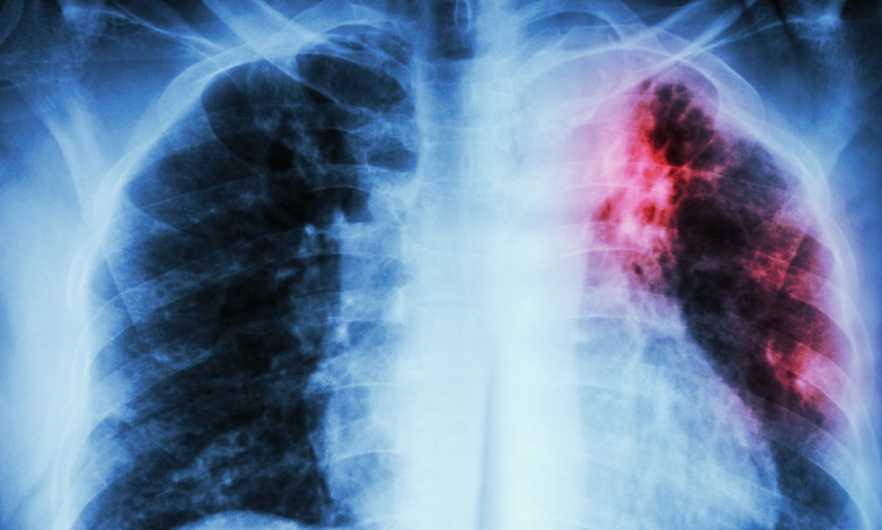

यसले विशेष रूपमा फोक्सोलाई असर गर्छ। साथै फोक्सो बाहेक अन्य अंगहरुमा पनि यो रोग लाग्दछ। क्षयरोग ८० प्रतिशत जति फोक्सोको क्षयरोग हुने भएकोले विरामीले श्वास फेर्दा हावामा कीटाणु फैलिन्छ।